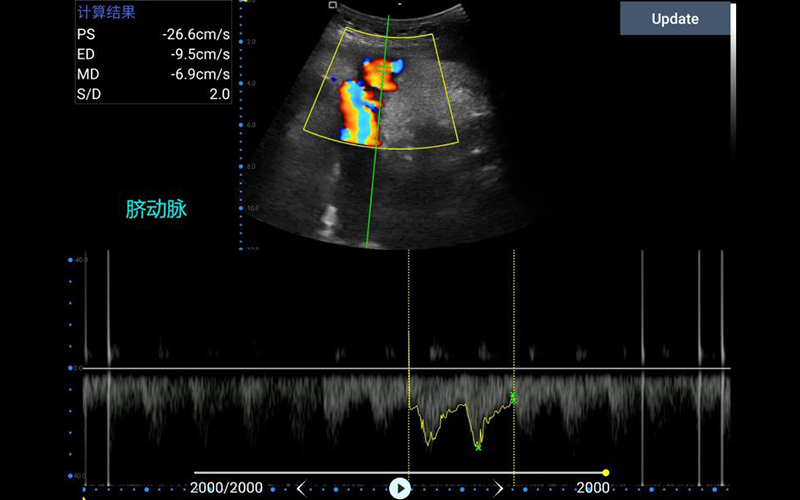

• 微凸

腹部

肾脏

新生儿颅脑

及心脏

小动物等